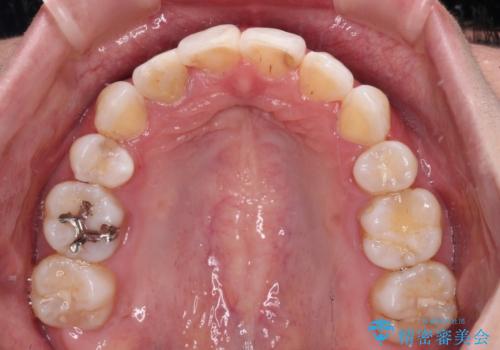

目立たないハーフリンガル矯正 抜歯矯正で口元を改善

- ハーフリンガル

期間はかかったものの、口元の張り出し感や歯のデコボコが解消され、患者様には大変満足していただけました。